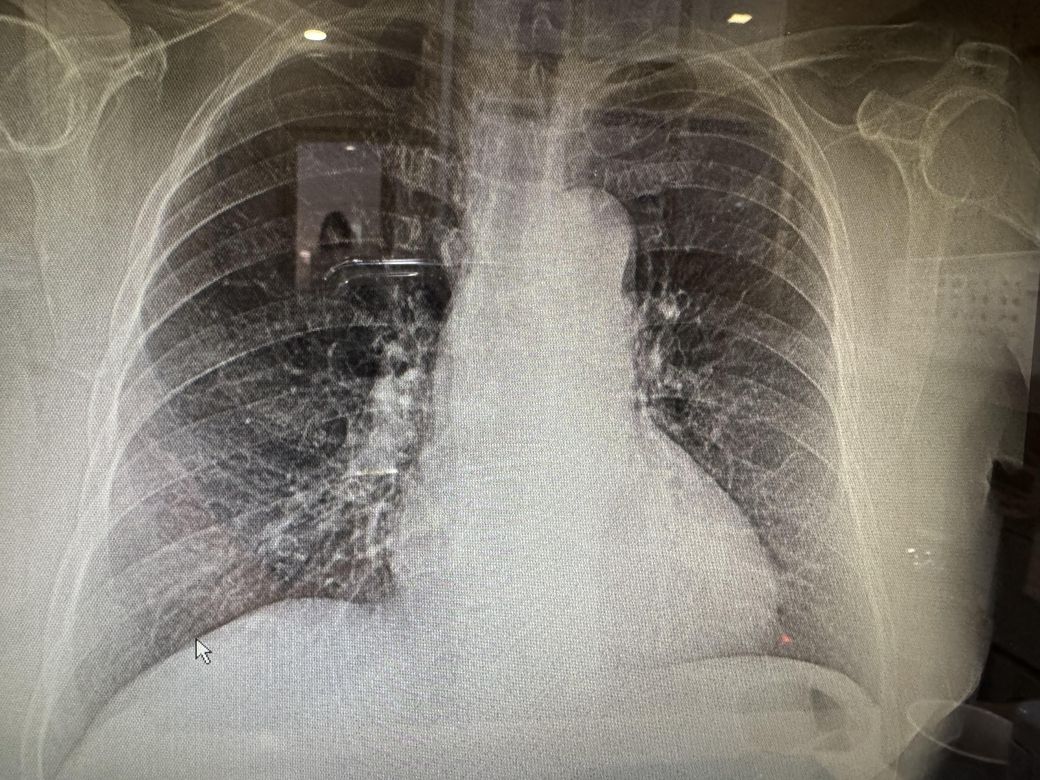

엑스레이 판독 부탁드려요 괜찮아보이나요?

기침증상이 좀 있는데 엑스레이상에는 문제 없을지 궁금합니다

X ray는 정밀검사는 아니고 사진도 깨끗하게 나오지는 않았지만, 전체적으로 큰 문제는 없어보이네요. 정밀검사가 필요하면 CT를 찍어봐야하지만,, 기침한다고 그정도 검사 필요하지는 않을거 같네요

• 사진을 PACS 상에서 직접 판독을 해야 정확하기에 명확히 진단을 내리기 어려우나 양측하단의 음영 증가가 있는 것으로 판단 됩니다. 폐부종 등이 있지는 않은지 내과 전문의 진료를 받아보시기 바랍니다.